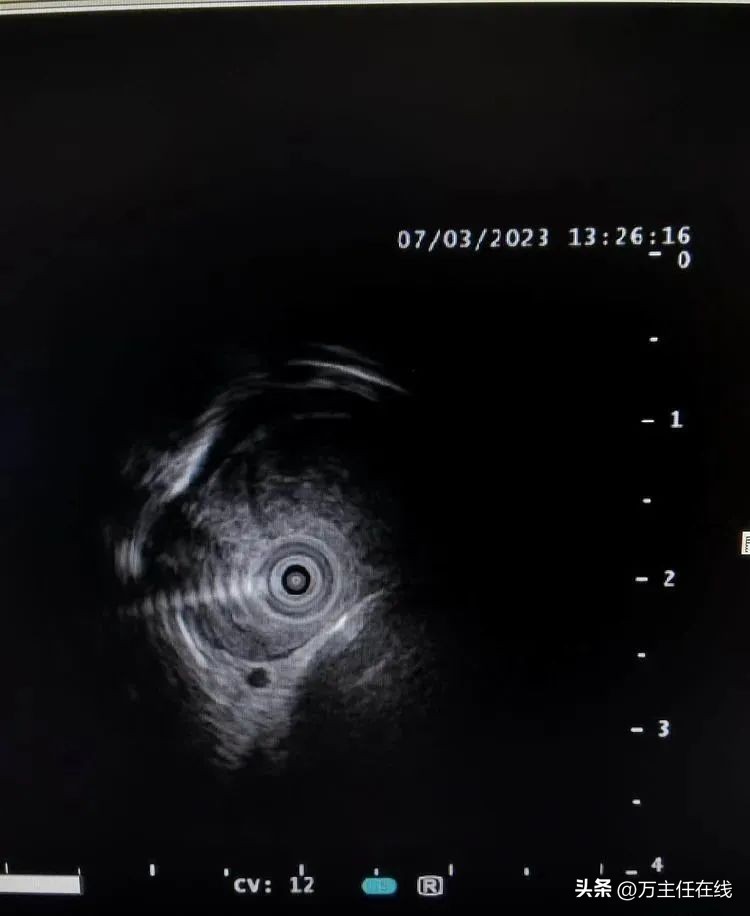

超声内镜发现起自食管固有肌层低回声占位并侵占纵隔、紧贴主动脉弓及分支动脉